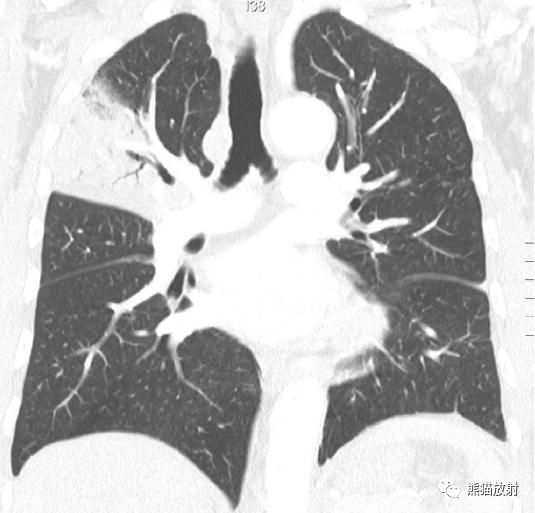

↑ 流感嗜血杆菌所致支气管肺炎

48岁男性,咳嗽咳痰,发热。右肺下叶局灶性实变影,边界不清,内见支气管充气征,同时伴有小结节和数个“树芽征”结节。